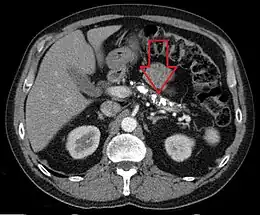

Scanner abdominal (coupe axiale) révélant de nombreuses calcifications dans le pancréas d'un patient présentant une pancréatite chronique.

Les calcifications du pancréas sont typiques de la pancréatite chronique. Elles sont vues au mieux sur un scanner sans injection.